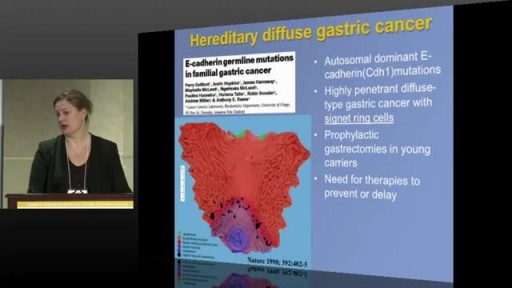

- Oncology and Cancers

- Gastroenterology